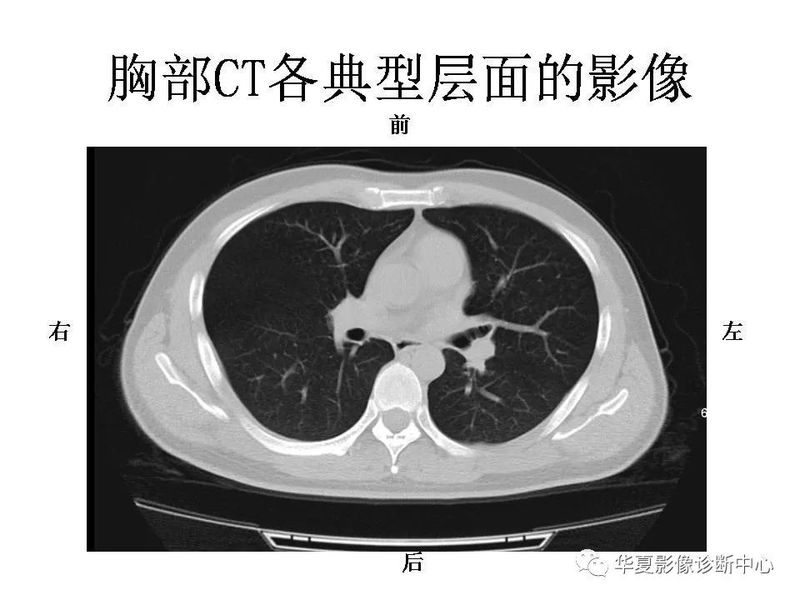

干货 | 汇总胸部CT读片扫盲知识,看懂胸部CT不再难